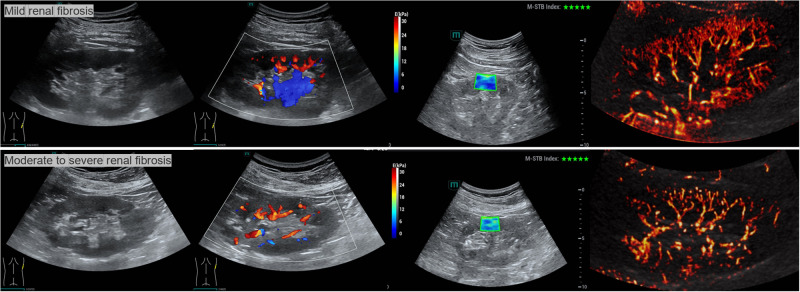

Objective: This study aims to evaluate the diagnostic efficacy of shear wave elastography (SWE) and super-resolution imaging (SRI) in detecting moderate-to-severe renal fibrosis (MSRF) among patients with chronic kidney disease (CKD).

Methods: In this prospective study, 202 CKD patients who underwent SWE and SRI prior to renal biopsy were enrolled. Based on pathological findings, patients were categorized into a mild renal fibrosis group (n=107) and an MSRF group (n=95). LASSO logistic regression was employed to identify independent risk factors for MSRF. Four diagnostic models-isolated, series, parallel, and integrated-were developed by combining elasticity values from SWE and vascular density values from SRI. Additionally, a nomogram incorporating clinical parameters and ultrasound composite parameters was constructed to assess MSRF in CKD patients.

Conclusion: The integration of SWE-derived elasticity and SRI-derived vascular density significantly enhances the diagnostic accuracy for MSRF in CKD patients. This comprehensive approach offers a promising non-invasive strategy for assessing renal fibrosis severity.